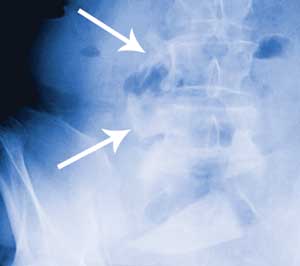

A Abdominal radiograph

A: A large triangular foreign body is visible in the pelvis. Note the deformity of the right transverse processes of L4 and L5 (arrows).

The abdominal radiograph was reviewed the day after clinical presentation and surgery. It was noticed that there was partial bony fusion of the right transverse processes of the fourth and fifth lumbar vertebral bodies. A CT scan confirmed that new bone formation at this level had produced a solid block of bone with a central defect in the shape of a rectangle. It is thought that the glass fragment snapped off deep to the skin and fractured the right transverse processes of L4 and L5, with the subsequent fracture healing process giving rise to a perfect bony cast of the fragment. It is well documented that a fracture initiates a sequence of inflammation, repair and remodelling, and that the remodelling process continues for years.1 Another CT scan showed the bony tract caused by the glass fragment projecting anteriorly into the right psoas muscle. Directly anterior to this, the terminal ileum could be seen lying on the anterior surface of the right psoas muscle (Figure, C). It is thought that the sharp end of the glass fragment gradually worked its way out the front of the psoas muscle and into the terminal ileum.